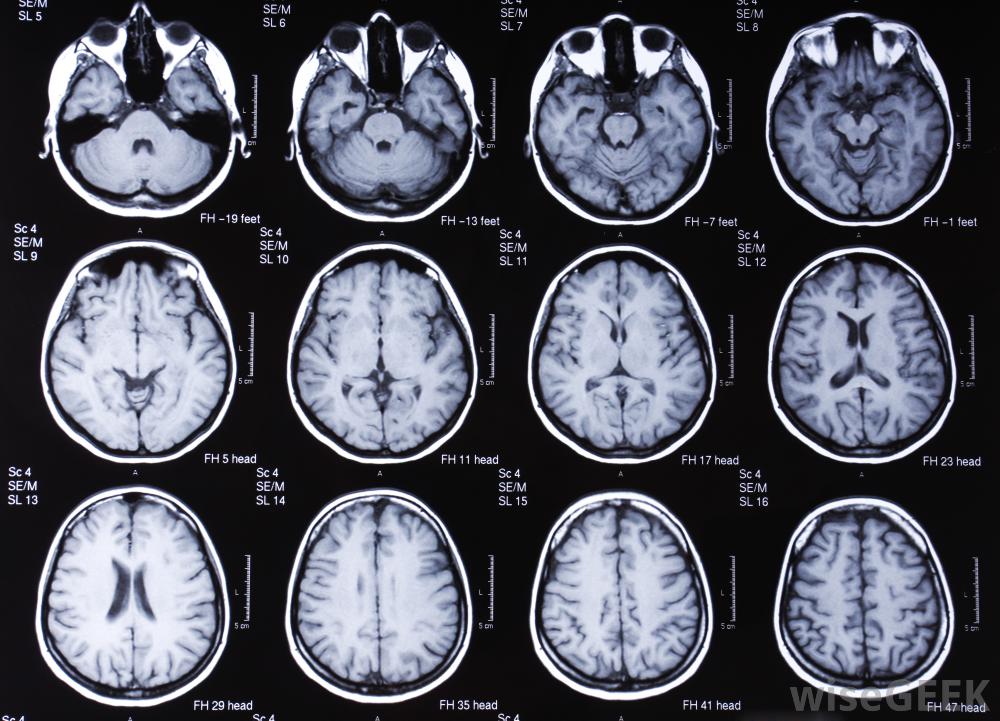

對大腦進行核磁共振掃描。

對大腦進行核磁共振掃描。核磁共振檢查前的鎮靜劑對藥物治療或身體狀況引起的抽搐或抽搐也有幫助,如不寧腿綜合征。核磁共振的鎮靜劑可以使病情平靜足夠長時間,以獲得必要的圖像。通常,口服鎮靜劑用于核磁共振掃描,但在更嚴重的情況下,靜脈滴注鎮靜劑或吸入鎮靜劑可用于使患者處于更深層的鎮靜狀態。